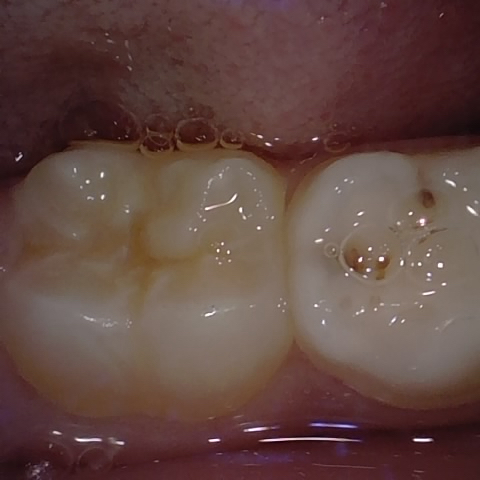

Annotated as "Good"

Original Image Rendering Image